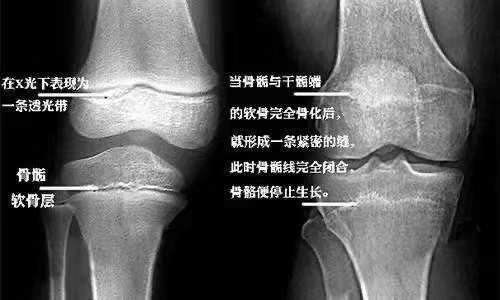

骨龄对比

孩子的健康成长,牵动着广大家长的心。孩子的生长发育有显著的季节性,其中以春季(3月-5月)的生长速度最快。在一般情况下,女孩骨龄在14周岁、男孩骨龄在16周岁时,骨骺线趋近闭合。骨骺软骨板已近消失,骨干与骨骺即将融合,生长潜力所剩无几。建议家长关注孩子身高,可以与同龄孩子或自己上一年的身高作比较,一旦发现孩子的生长速度不正常,尽早至专科门诊就诊,医生会通过身高、骨龄、生长发育状况等进行综合评估。